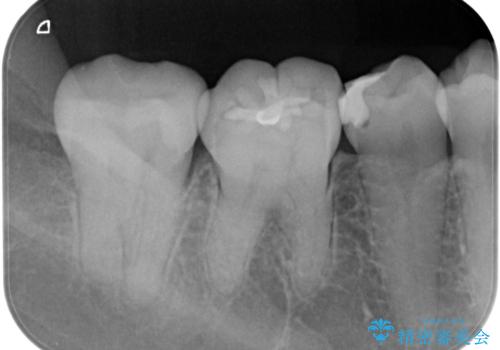

歯に食べ物が詰まる。

- 歯に食べ物が詰まるとの事で来院。

虫歯により歯が欠けていたので拡大鏡下で虫歯を除去した後、セラミックの詰め物で治療しました。

適合の良い詰め物が入りました。

セラミックスは虫歯の再発のリスクが低くなります。